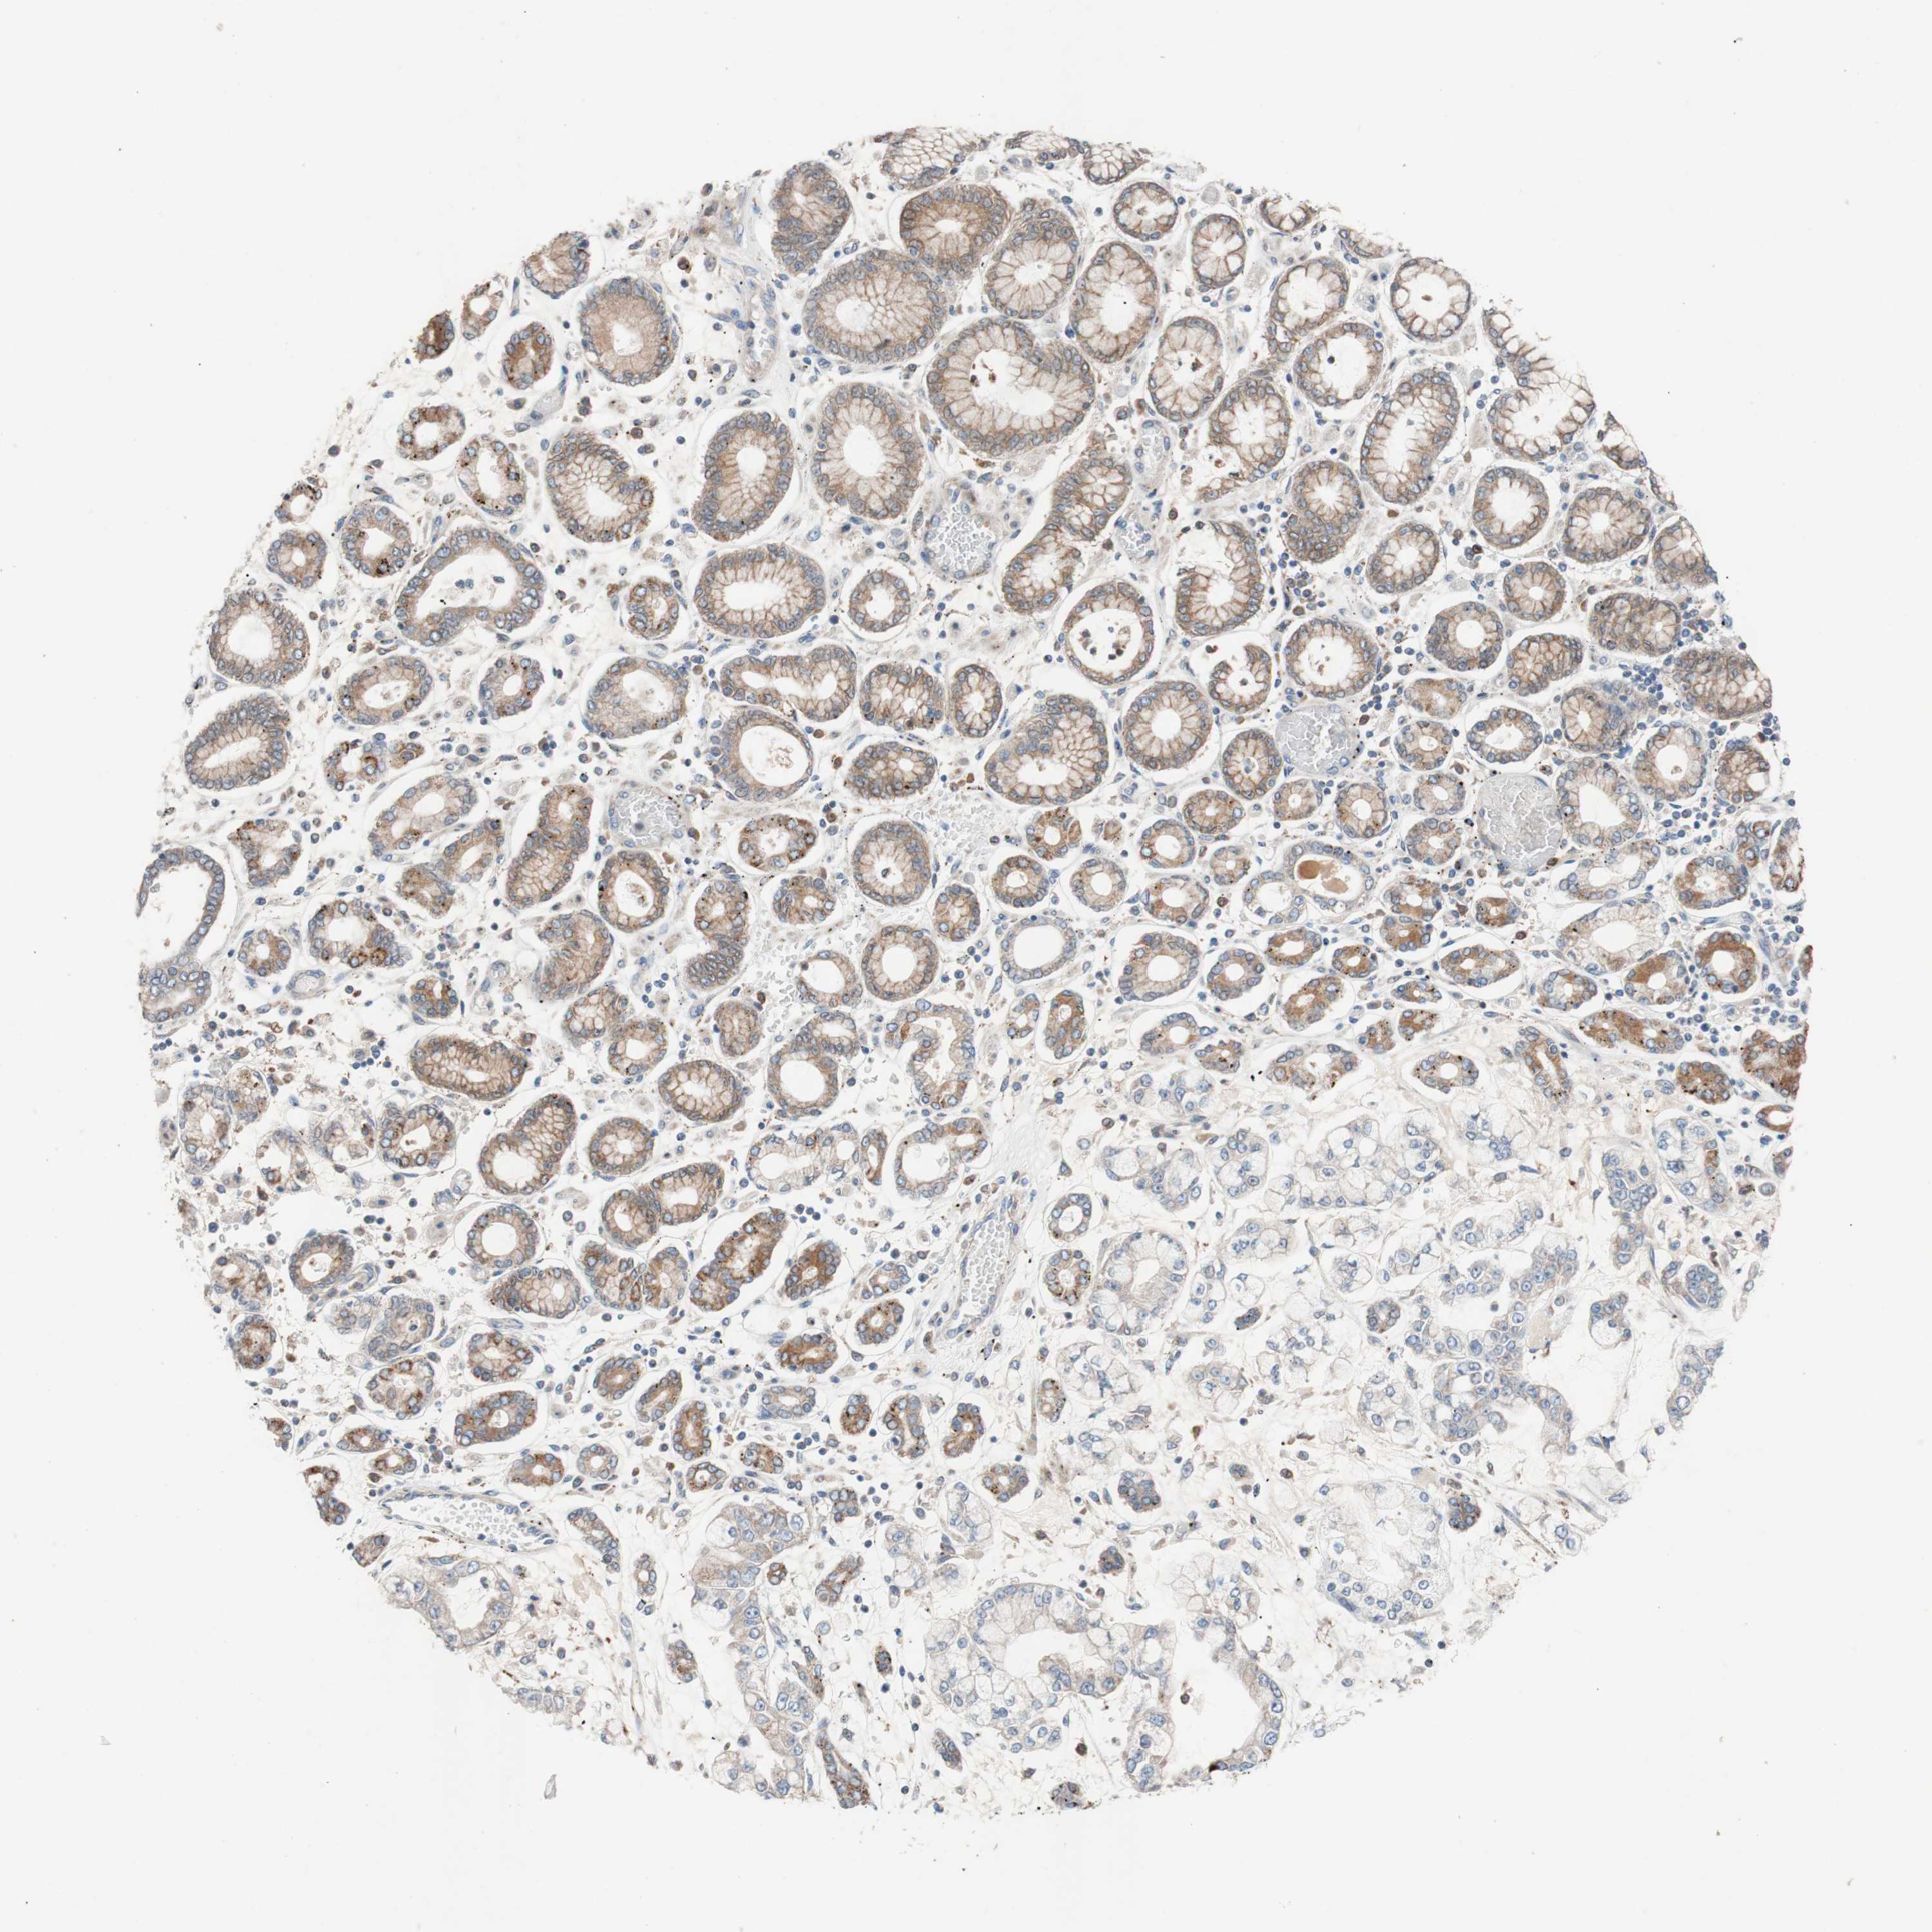

STOMACH CANCER - Protein expressioni

A mouse-over function shows sample information and annotation data. Click on an image to view it in a full screen mode. Samples can be filtered based on level of antibody staining by selecting one or several of the following categories: high, medium, low and not detected. The assay and annotation is described here.

Note that samples used for immunohistochemistry by the Human Protein Atlas do not correspond to samples in the TCGA dataset.

Antibody stainingi

Antibody staining in the annotated cell types in the current human tissue is reported as not detected, low, medium, or high, based on conventional immunohistochemistry profiling in selected tissues. This score is based on the combination of the staining intensity and fraction of stained cells.

Each image is clickable and will lead to virtual microscopy that enables deeper exploration of all samples and also displays staining intensity scores, fraction scores and subcellular localization as well as patient and tissue information for each sample.

Antibody HPA007425

Staining

High

Medium

Low

Not detected

Intensity

Strong

Moderate

Weak

Negative

Quantity

>75%

75%-25%

<25%

None

Location

Nuclear

Cytoplasmic/membranous

Cytoplasmic/membranous,nuclear

Adenocarcinoma, NOS

Adenocarcinoma, High grade